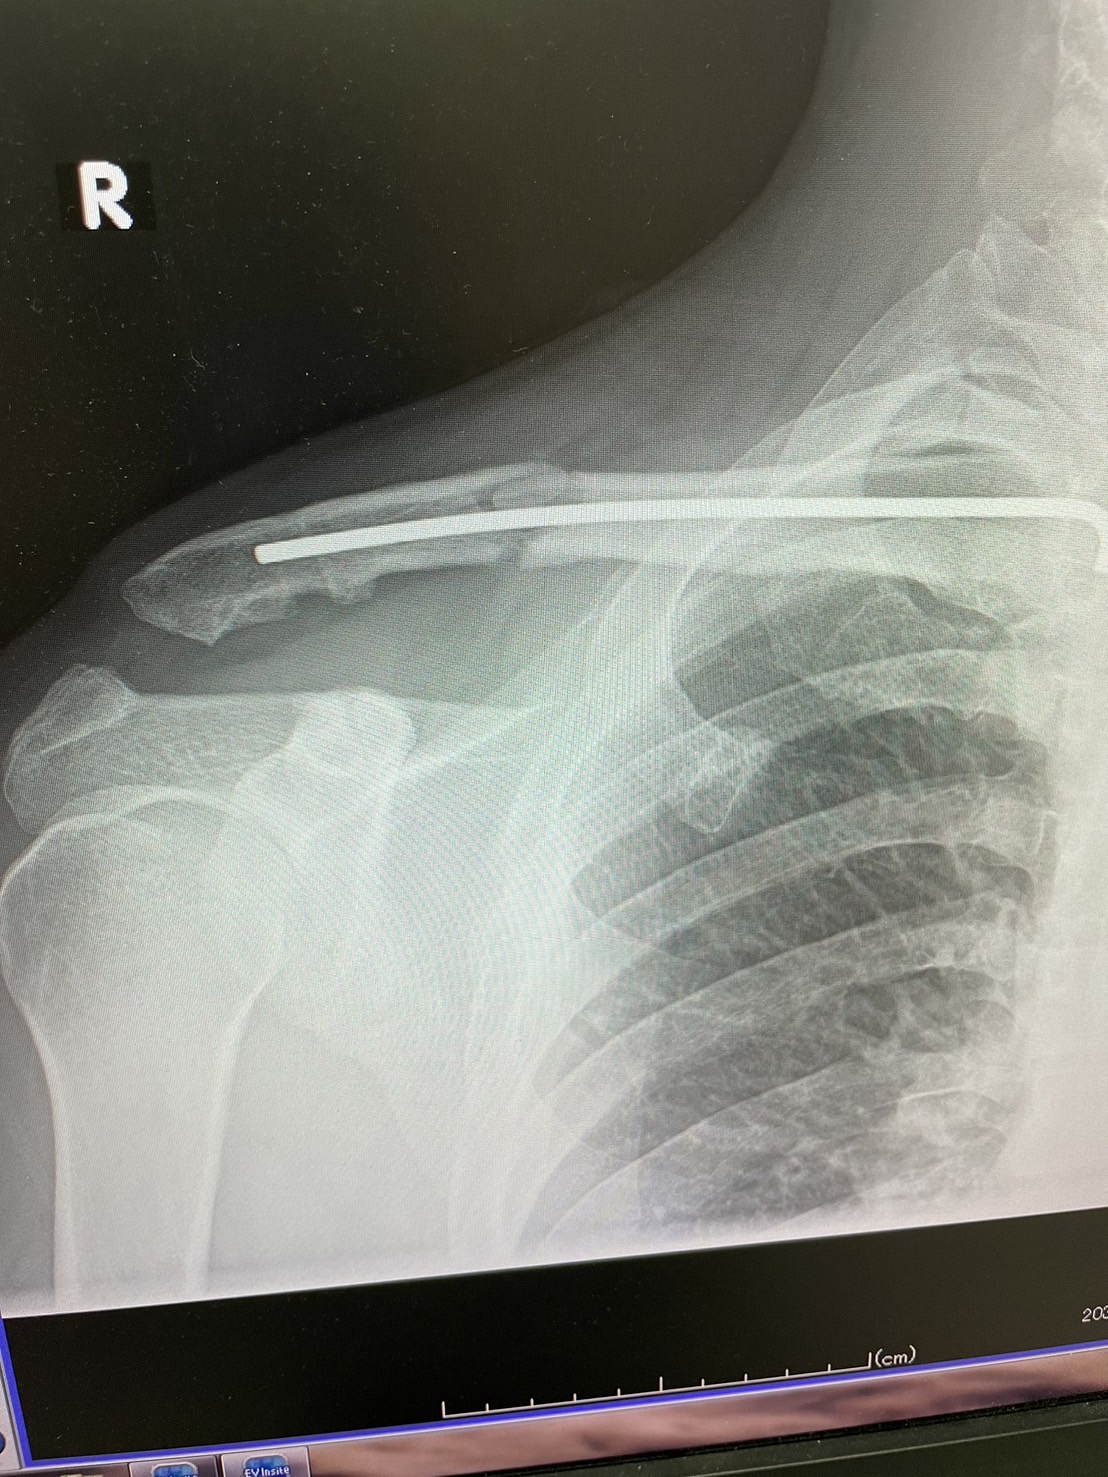

競輪選手になってからはそこまで大怪我はせず順調だったのですが、今年の2月と5月に落車をしてしまい、鎖骨・肋骨・肩甲骨を骨折してしまいました。

鎖骨には、手術でピンのようなものも入れてあるのですが、それも今月で抜けました。